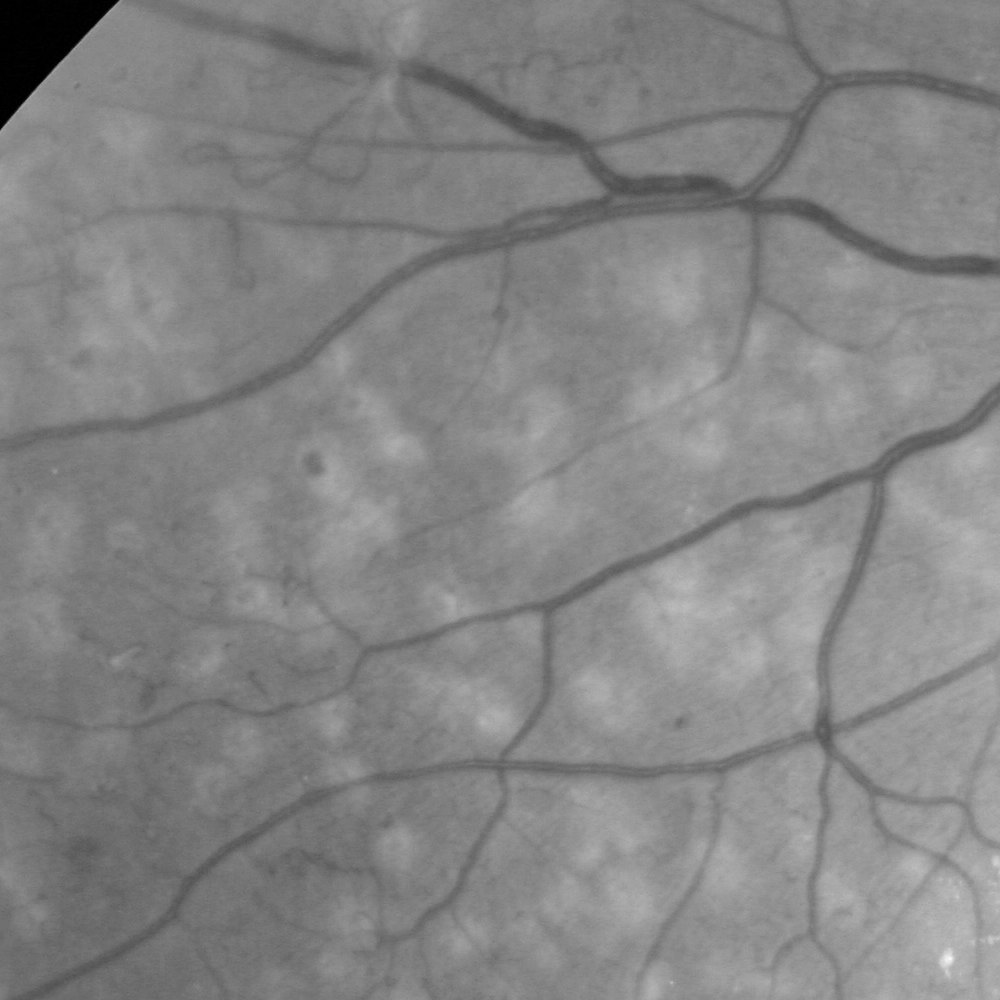

Fig. 4 shows a qualitative ablation study: it illustrates that the intensity representation may miss large vessels in the very high-resolution HRF images, while remains robust. In contrast, provides sharper delineation for very thin vessels in ROSE. The fusion of both pathways outperforms either pathway for most scenarios. These observations are further supported by the quantitative ablation study in Fig.6. We note that and can be used as synthetic angiograms that provide both enhanced vessel visualization and model interpretability.